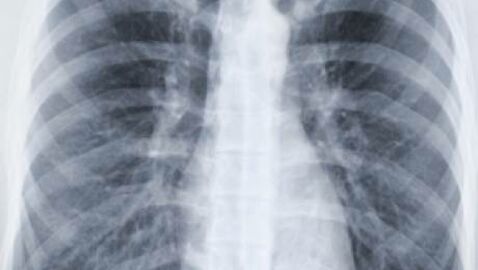

Dans cette prison, un programme d’intelligence artificielle (IA) se révèle être un nouvel outil crucial dans la détection de la tuberculose. Un détenu, vêtu d’un tee-shirt orange marqué du terme « détenu », se tient face à une grande tablette blanche fixée au mur. Derrière lui, un infirmier déclenche un appareil portable à rayons X connecté à un logiciel d’IA, marquant une étape révolutionnaire dans la lutte contre cette maladie infectieuse qui cible généralement les poumons.

Le programme d’intelligence artificielle analyse instantanément et avec précision les résultats des radiographies pulmonaires, évitant ainsi le recours à l’expertise directe d’un médecin. Cette technologie innovante permet d’interpréter rapidement les données radiologiques, facilitant ainsi le dépistage précoce de la tuberculose sans attendre l’intervention d’un spécialiste.